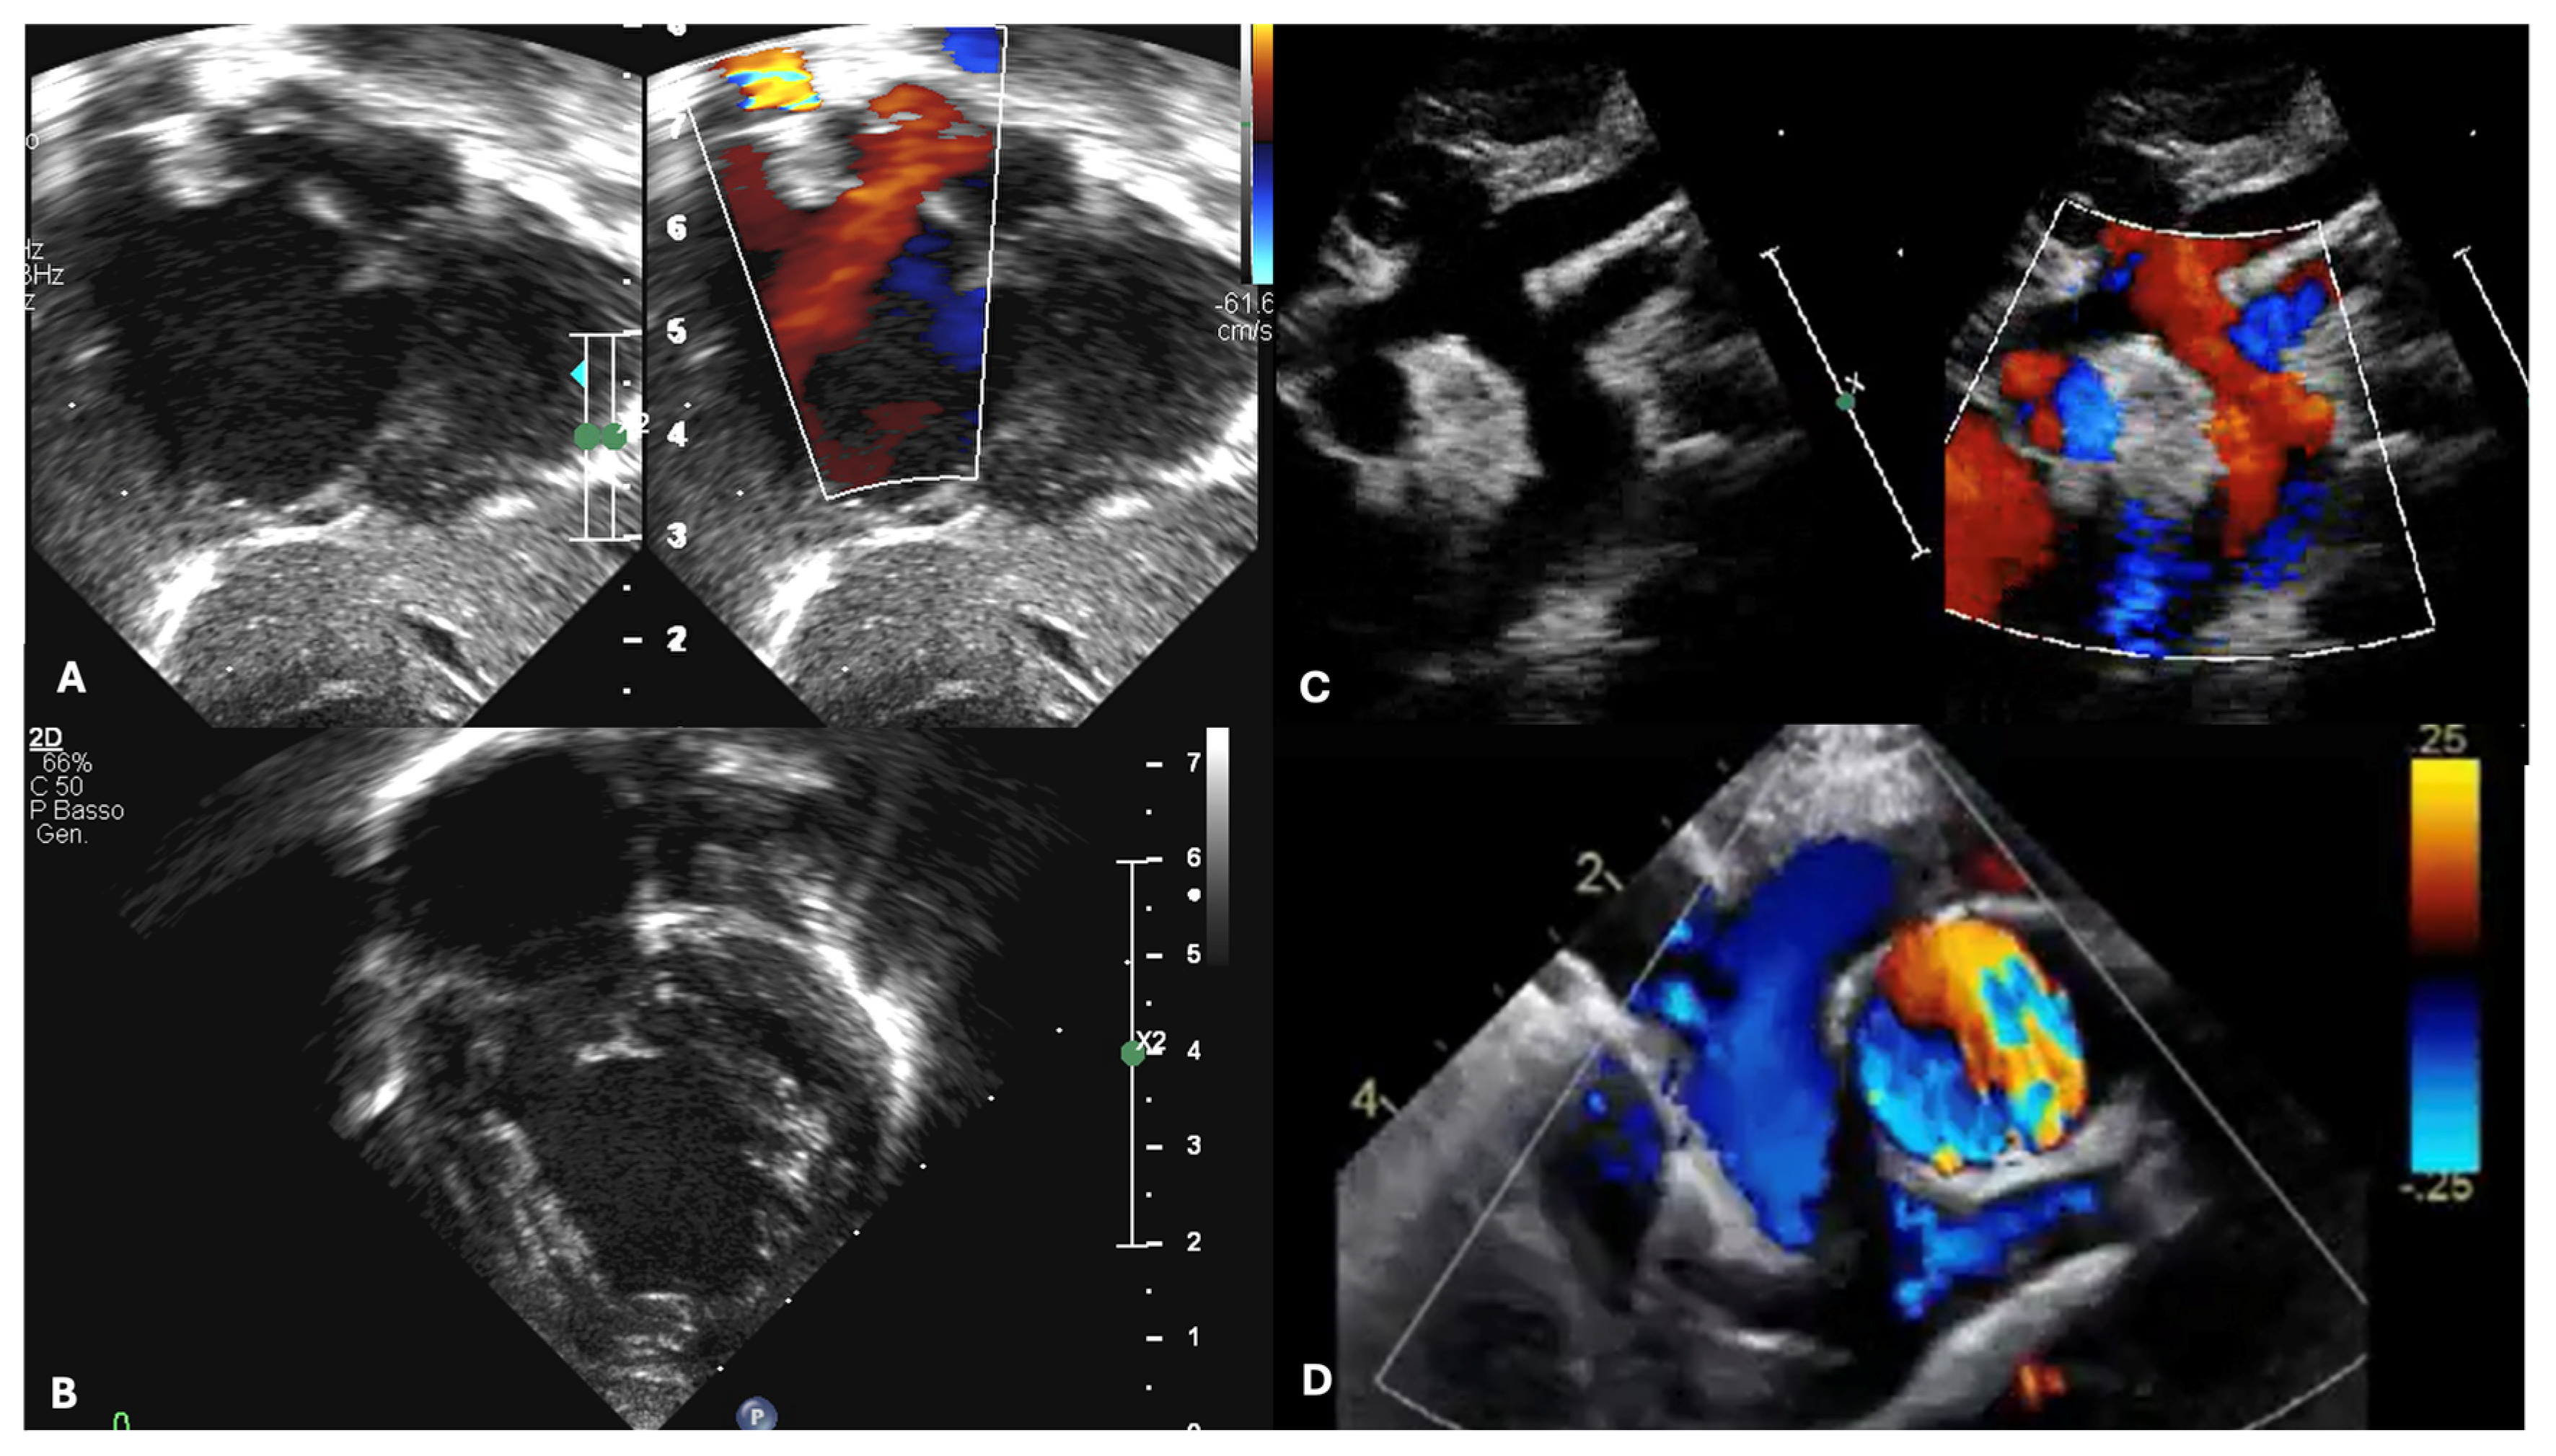

3. Multimodal Assessment During Neonatal and Pediatric Life Until TCPC Completion